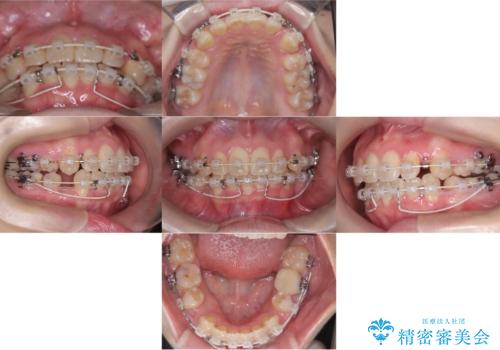

- 「歯のデコボコ、八重歯、口ボコが気になる」を主訴に来院された患者様です。

上下左右4番(4本)の歯を抜歯しワイヤー矯正で治療を行いました。

計4本の抜歯を行い、歯のデコボコと口元がすっきりし、大変ご満足していただけました。